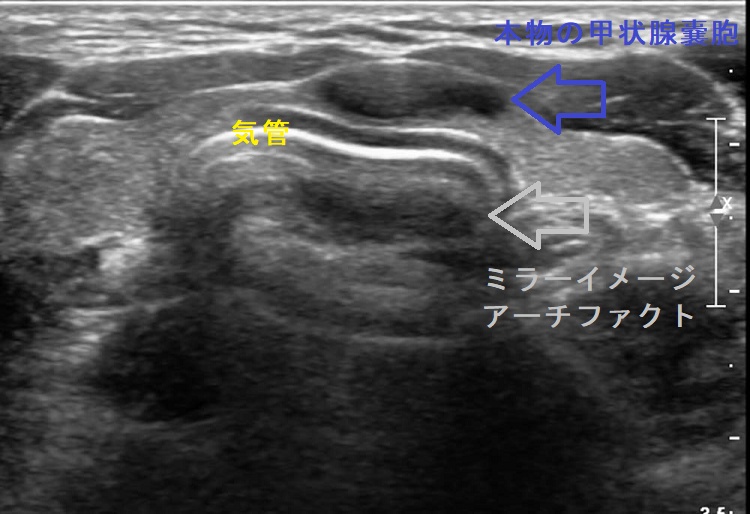

気管に近接する甲状腺嚢胞(のう胞)では、超音波(エコー)検査においてミラーイメージ アーチファクトを生じるケースがあります。過度に収縮して超音波(エコー)を反射しやすくなった気管壁から跳ね返ってきた反射波が、周囲の構造物に当たり、再度気管に向かう2重の反射波が原因(鏡面反射の原理)。この現象により、2重の反射波が時間差を置いて帰ってくるため、気管壁の内側(気管内腔)に同じエコー像が現れます。

もちろん、現実には存在しないアーチファクトなので、頸部CTには写りません。穿刺排液で甲状腺嚢胞(のう胞)が縮小すればミラーイメージも縮小します。

[Radiol Case Rep. 2018 Feb 9;13(2):408-410.]